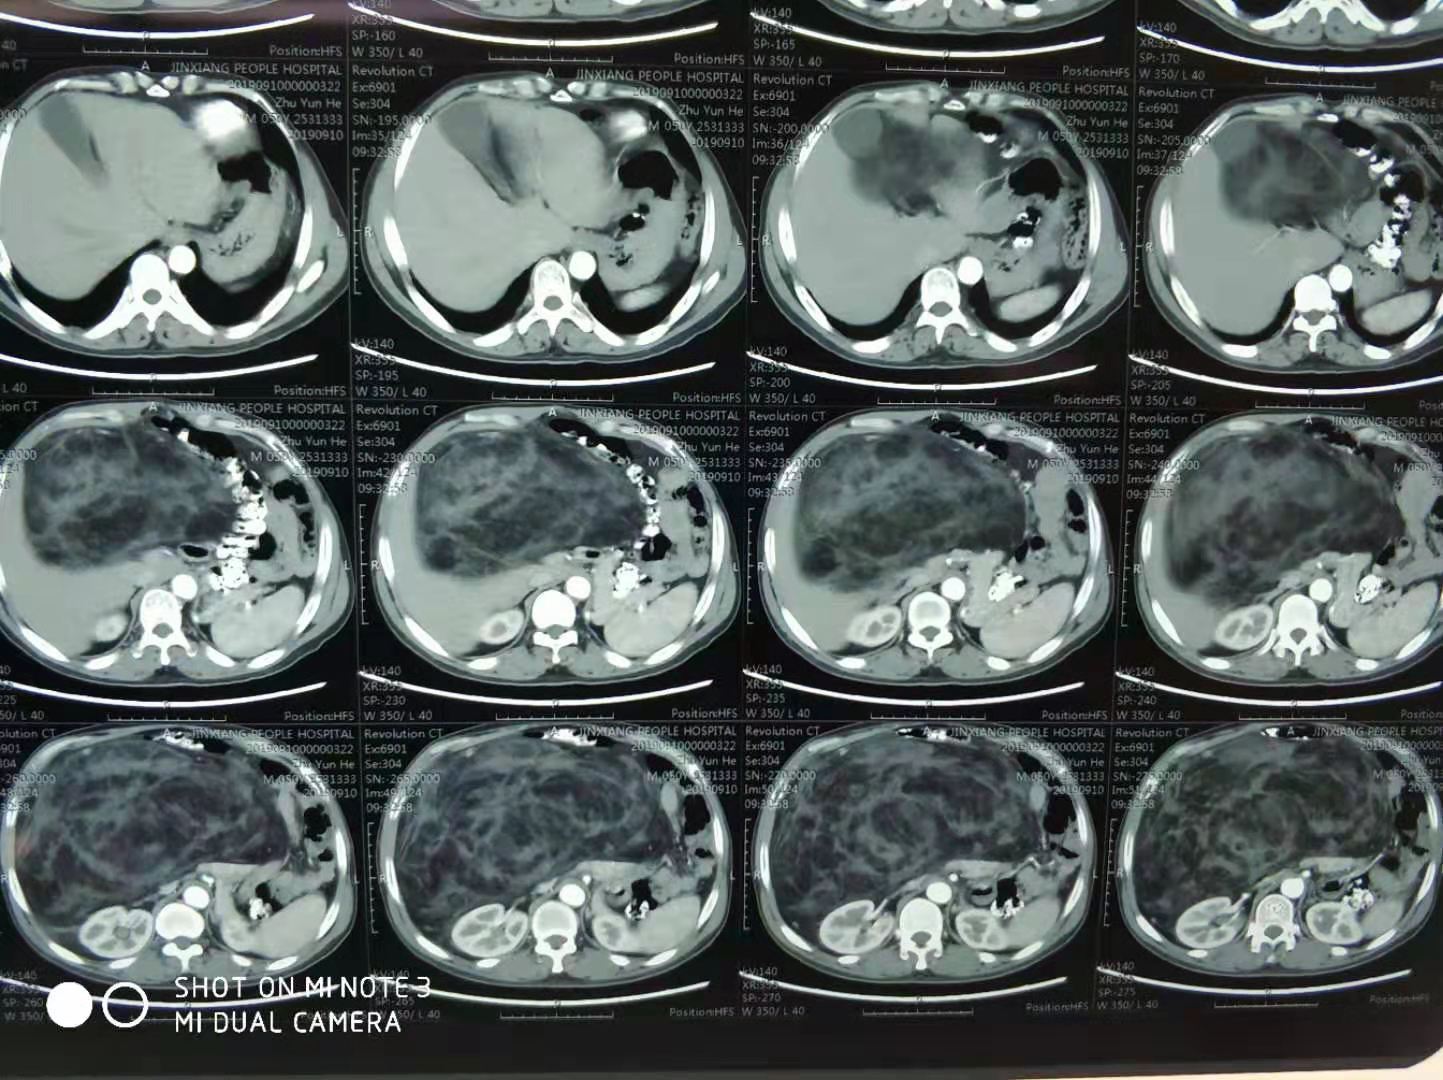

入院后,经过详细的检查,发现马先生的腹腔内藏有一个直径约30cm的巨大肿瘤!

CT显示巨大的肿瘤几乎占据了整个腹腔,周围脏器受到了严重的挤压。

在经过细致充分的准备后,9月12日上午9点05分,按计划为马先生实施了“腹腔后脂肪肉瘤切除术”,在麻醉医师和手术护士的紧密配合下,只用了不到2个小时的时间就将这个巨大的肿瘤从马先生体内完整摘除,整场手术非常顺利,术中出血少,患者各项生命体征平稳,10点58分手术结束后患者安返病房。经测量,此次从马先生体内取出的肿瘤体积为30*28*12cm,呈实性,瘤体重达13斤!实属罕见!